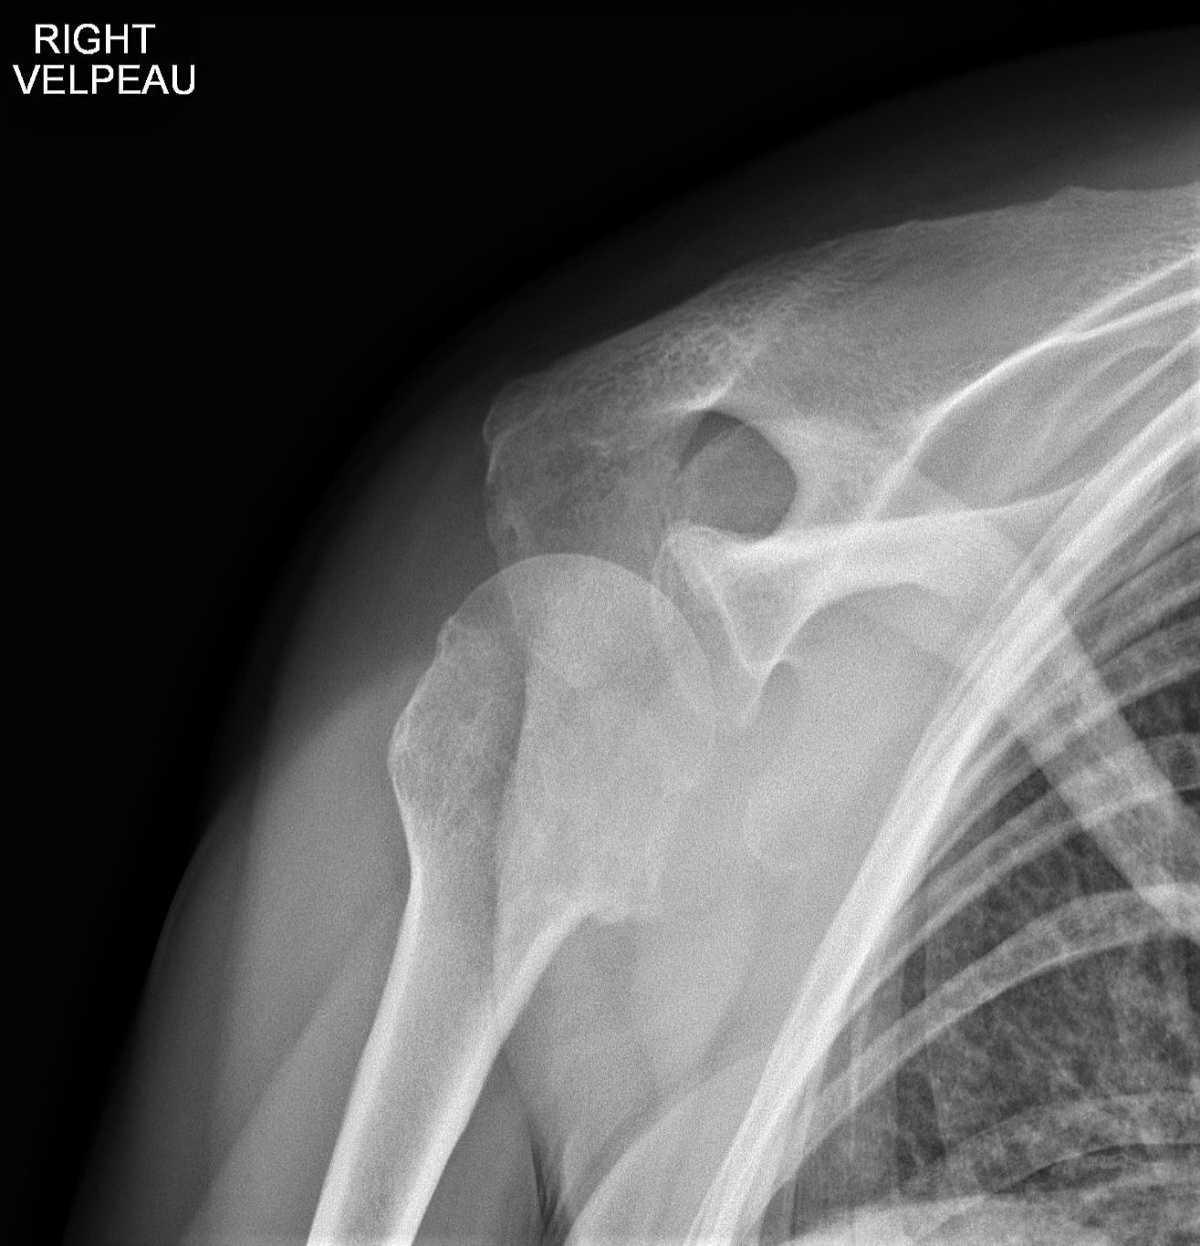

Hellerhoff - Own work, CC BY-SA 3.0, Link

Radio de l’épaule (F + profil de Lamy)

Aspect radiologique PIEGEUX:

- disparition de l’interligne articulaire (trop bel aspect sphérique de la tête humérale)

- cliniquement : rotation externe impossible (signe de l’aumône)